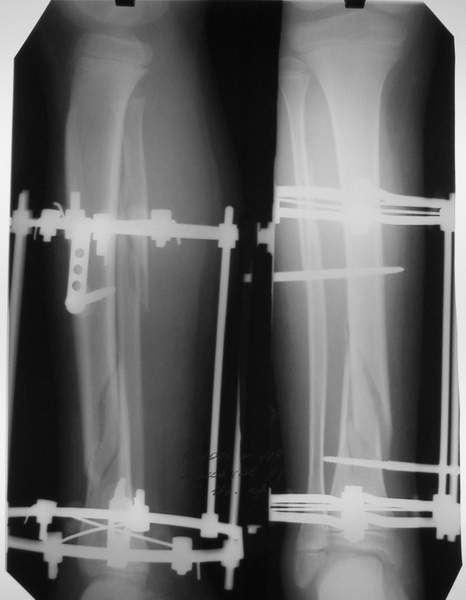

В аттачтах №№ 1 и 2 - примеры, когда 2 кольца не позволили послеоперационно

исправить смещение фрагментов большеберцовой (по ширине и вальгусное).

А казалось бы (#2) - поиграй на штангах и все влетит.

Оперировал не я